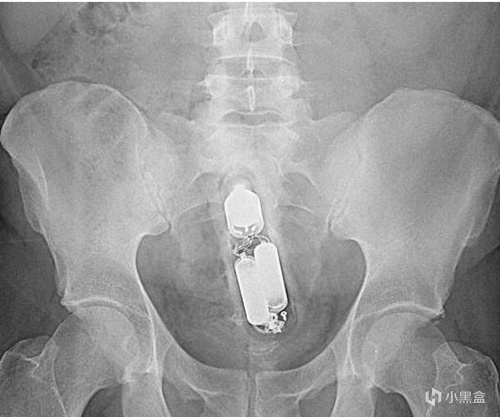

上面有我接診過的患者,也有來源網絡的圖片。但是這種誤入體內的異物,可能有電子產品或者瓶子,甚至也有活物進入的情況。大多數直腸異物發生sex的過程中,被取出的異物包括但不限於按摩棒,橡膠聖劍、高爾夫球、白熾燈等等(也經常有毒販通過包裝好的袋裝毒品藏入胃裏或者直腸裏來販毒)。有一些異物可能一開始已經被完全容納進去,深入體內後難以取出。

比如這位患者在嘗試用夾鉗自救取出異物,可惜一起折戟在體內了不得已就診。

直腸異物典型症狀就是排便困難、腹痛、便血,甚至腸梗阻。如果嘗試自救,反覆磨蹭還可能導致肛管、直腸部分的黏膜水腫和肌肉痙攣,進而更難取出異物。而且最好不要輕易嘗試在不確定異物種類和位置的情況下,做直腸檢查。要不然容易導致異物破裂,造成二次傷害。

一般在直腸鏡下通過夾鉗和牽引取出位置較低的異物,高位的就需要結腸鏡和手術取出了。總結來說,這屬於人禍導致的,無論是否是自己主動塞進去異物,最後都需要儘早解決。